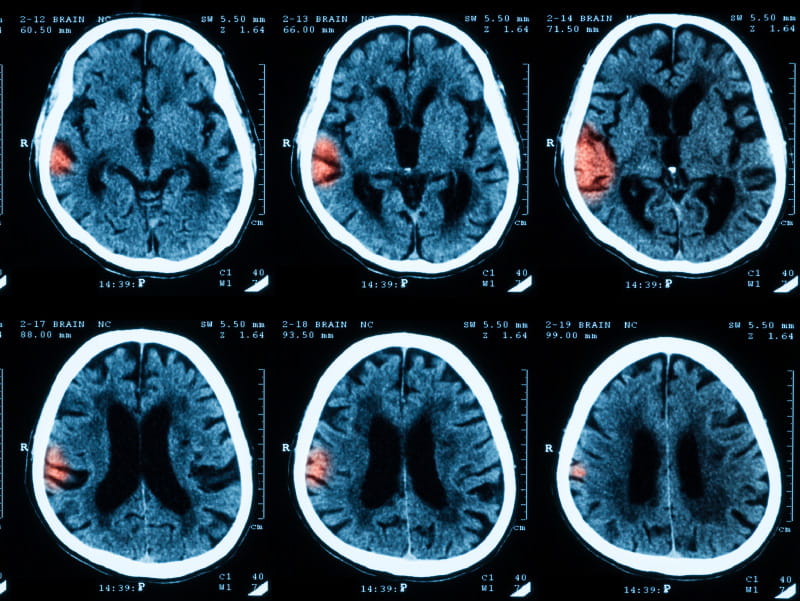

Studies have shown an association between clot-caused ischemic stroke, the most common type, and fine particulate matter such as air pollution from car exhaust. But few, if any, have investigated how air pollution like ground-level ozone impacts intracerebral hemorrhage, a bleeding type of stroke which accounts for about 10 percent of all strokes and happens when a weakened vessel ruptures into the surrounding brain.

An estimated 40,000 to 67,000 Americans have an intracerebral hemorrhage each year, with often devastating results. Between a third and half of patients die within a month – and only one in five survivors recover fully within six months.